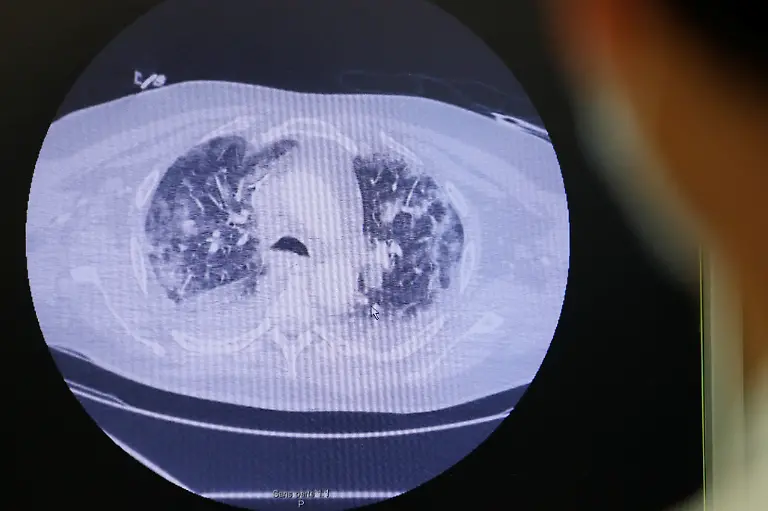

In unzähligen Krankenhäusern weltweit sind die Intensivstationen der Ort, wo sich das Schicksal der schwer erkrankten Covid-19-Patienten entscheidet. Die Ärzte und Pflegenden dort leisten beinahe Übermenschliches. Sie sind oft die einzigen, die in der Stunde des Todes bei den Patienten sein können. Jeder Patient, der nach Wochen auf dem Weg der Besserung entlassen werden kann, wird gefeiert.